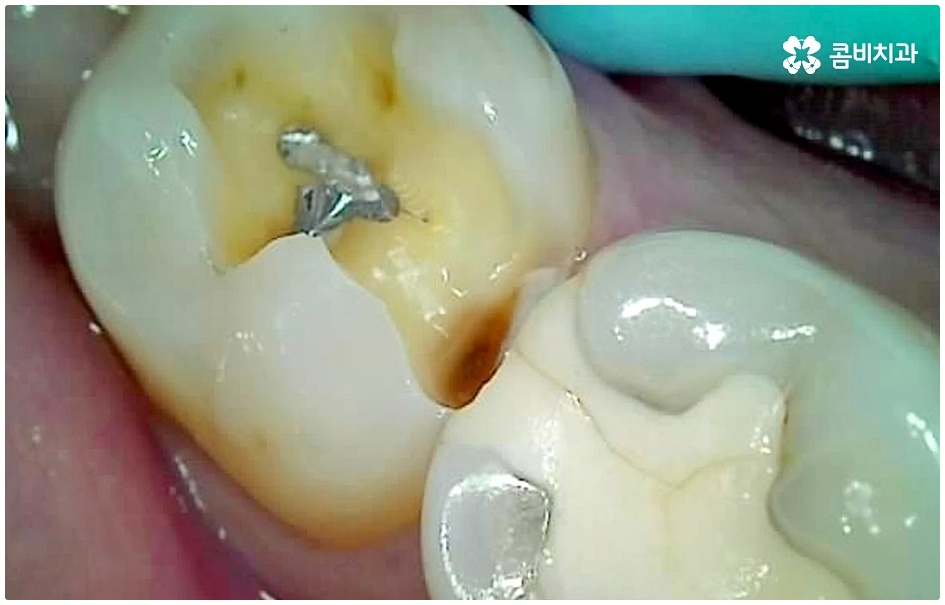

이 때 교합면, 즉 치아의 씹는 면이 아닌 치아 사이 충치가 생겼다면 쉽게 발견하기도 어렵고 치료를 위한 접근 역시 까다롭기 때문에 주의하실 필요가 있습니다. 물론 가장 흔하게 발생하는 것은 넓고 홈이 파여 있으며 직접 음식물을 저작하는 교합면에 생기는 충치일 것이나 음식물 찌꺼기가 끼기 쉽고 세균이 서식하기도 쉬우며 양치질을 하더라도 칫솔모가 잘 닿지 않기 때문에 관리가 어려운 치아 사이 좁은 틈새에도 역시 충치가 잘 생길 수 있는 거예요.

치아 사이 충치는 치아끼리 맞닿아 있는 부분이라 노출이 잘 되지 않기 때문에 육안으로 식별이 어려운 경우가 많은데, 만약 눈으로 확인될 정도라면 질환이 이미 많이 진행한 상태이므로 명동치과 에서 빠른 치료를 받아주실 필요가 있어요.

치아의 구조를 살펴보면 겉표면인 단단한 법랑질은 교합면에서 가장 두껍고 잇몸쪽으로 갈수록 얇아지기 때문에 치아 사이의 인접면은 치아의 신경과 한층 가까워서 충치가 조금만 진행되어도 신경치료를 받아야 할 수 있으며 인접면 충치가 심하여 레진이나 인레이 수복으로 치아의 외형을 재현하기 어려운 경우에는 치아 전체를 다듬어 씌우는 명동치과 크라운 치료를 해줘야 하니 부담이 커지기 전에 치료 시기를 놓치지 않도록 주의하시는 게 좋을 거예요.